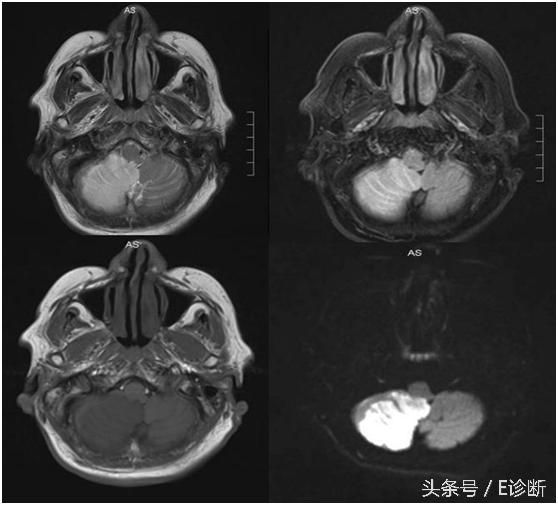

脑桥梗塞,发病3天,T1WI为稍低信号,T2WI及flair像为高信号,DWI为高信号。

右侧小脑梗塞,发病3天,T1WI为稍低信号,T2WI及flair像为高信号,DWI为高信号。